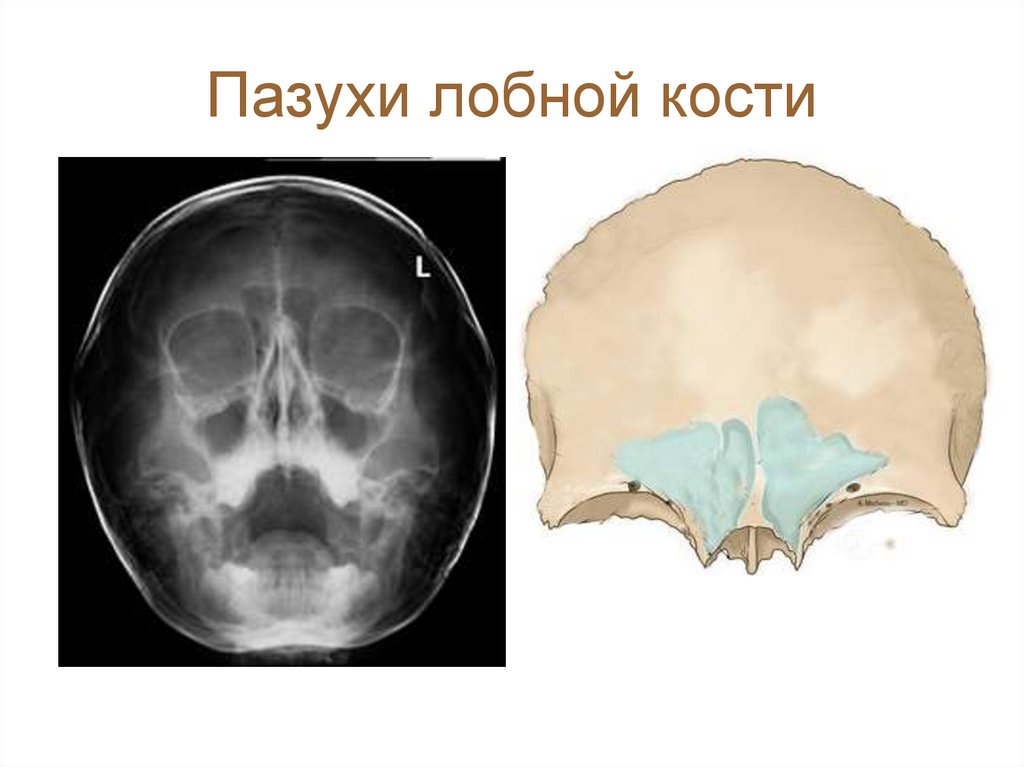

49. Пазухи лобной кости

Лобная пазуха, содержащая воздух, разделена обыкновенно